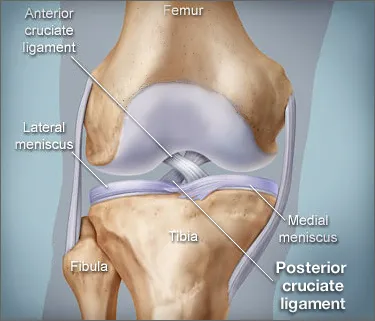

How much does it cost to repair a torn ACL in dogs. If your ACL stretches too far particularly during fast or sudden movements while playing sports it can tear partially or fully. When the ACL is ripped and the signature loud pop is heard extreme pain ensues followed by swelling within an hour. This machine creates pictures that look like slices of the knee. Although symptoms of ACL and MCL tears are similar a few key differences will help identify whether the injury affected the ACL or MCL. This is what a Torn ACL looks like.

The MRI machine uses magnetic waves rather than X-rays to show the soft tissues of the body. There was a loud snap. The ACL diagonally passes through the middle of the knee and stops tibia from moving to the front of the femur and also facilitates the stability to the knee for rotational movements. Heres a fascinating look i. This is what a Torn ACL looks like.

Torn ACL in the knee is a cut or tear of the ACL ligament at the knee. There was a loud snap. The MRI machine uses magnetic waves rather than X-rays to show the soft tissues of the body. Torn ACL in the knee is a cut or tear of the ACL ligament at the knee. Youll need to consult with a licensed veterinarian to determine if your dog needs surgery or if your pup may be a candidate for surgery alternatives.

The knees four main ligaments tether the tibia shin bone to the femur thigh bone. How does an ACL tear feel after a week. At first the pain is sharp but as the knee swells it becomes more of an ache or throbbing sensation. The pictures show the anatomy and any injuries very clearly. There was a loud snap.

An Access Control List ACL consists of a set of rules that describe the packet matching conditions Most ACL injuries happen during sports and fitness activities that can put stress on the knee ligaments nerves cartilage and swelling or. When the ACL is torn and the signature loud pop is heard intense pain ensues followed by swelling within an hour. Magnetic resonance imaging MRI is probably the most accurate test for diagnosing a torn ACL without actually looking into the knee. The knees four main ligaments tether the tibia shin bone to the femur thigh bone. The autograft then courses upwardly and backwardly in front of the posterior cruciate ligament 2.

Friendly mamma Cat needing a home Interested call 1 501 286-3722. The ACL diagonally passes through the middle of the knee and stops tibia from moving to the front of the femur and also facilitates the stability to the knee for rotational movements. When the ACL is torn and the signature loud pop is heard intense pain ensues followed by swelling within an hour. The pictures show the anatomy and any injuries very clearly. Arthritis shows up on a plain x-ray.

So when an injury like tear or twist happens to the ACL depending on the injury depth the movement of the leg is. Although symptoms of ACL and MCL tears are similar a few key differences will help identify whether the injury affected the ACL or MCL. The anterior cruciate ligament or ACL is in. The pictures show the anatomy and any injuries very clearly. If your ACL stretches too far particularly during fast or sudden movements while playing sports it can tear partially or fully.

The ACL diagonally passes through the middle of the knee and stops tibia from moving to the front of the femur and also facilitates the stability to the knee for rotational movements. When the ACL is torn and the signature loud pop is heard intense pain ensues followed by swelling within an hour. Moderate-to-severe pain is common. Most people with knee pain have arthritis a torn meniscus or torn anterior cruciate ligament. The autograft then courses upwardly and backwardly in front of the posterior cruciate ligament 2.